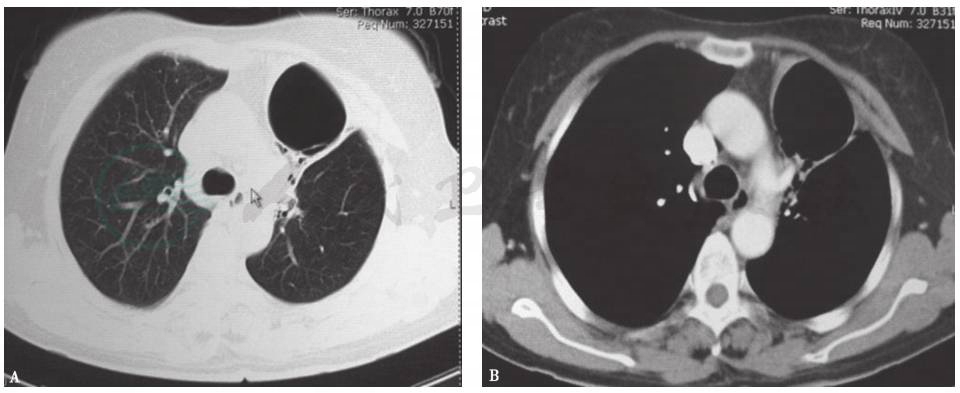

胸部CT可见左肺上叶大片状高密度渗出实变影,左肺下叶及右肺多发散在小片状高密度渗出灶(图1);随着病情发展,可见左上肺实变阴影内囊泡影(图2)。

图1 胸部CT表现(2010-01)